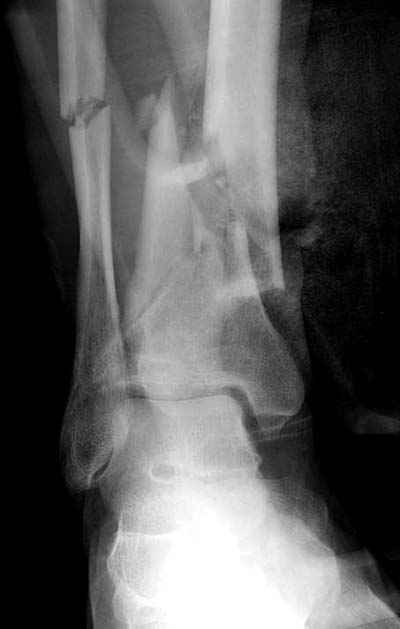

Разбор тактики лечения низких переломов костей голени становится популярной темой. Споры не только по тактике "по данным некоторых зарубежных авторов, при переломе обеих костей голени на одном уровне рекомендуется фиксация обеих", а также по импланту (гвоздь или пластина) и по локализациям имплантов "укладывать на заднюю поверхность при низких переломах"

Во всех описанных случаях единственное, что объединяет, это локализация перелома, а так это различные по механизму травмы. Различные импланты, и хирургическая техника отличается друг от друга. Разные по возрасту и по активности больные. Поэтому из-за невозможности создать единый алгоритм "до сих пор идет дискуссия".

Возвращаясь к разбору "БИОС у пожилого пациента", тогда многие из наших коллег проголосовали за то, чтобы оставить на одном интрамедуллярном гвозде. На рентгене плохое качество кости (остеопороз), костные фрагменты в середине канала, и на малоберцовой имеются фрагменты по линии перелома. В таких случаях гвоздь идеальный фиксатор, потому что создается равномерная компрессия на обе кости. А латеральная фиксация на малоберцовой, как распорка, повела бы в варус.

Данная фиксация пластинами сделана классическим АО методом описанным еще в 1989 году в книге J. Mast и R. Ganz “Planning and Reduction Technique in Fracture Surgery”. В то время antiglade method DCP пластиной в 4.5 мм c повторением натурального изгиба голени в н/3 считался одним из оригинальных. Повторение оригинальной концепции и фиксация спонгиозными шурупами в дистальном отделе доказывает, что коллеги хорошо освоили метод АО. Но для уменьшения раздражения пластиной изнутри в нижнем отделе, авторы применяли технику погружения пластины в кортекс. Профилактические меры не всегда помогали, и в неумелых руках "передне-медиальный АО доступ" часто осложнялся кожными осложнениями.

Без современных материалов создать хорошую фиксацию становится трудной задачей, и этот случай характерен тем, что достигнутую идеальную репозицию испортили старомодной техникой. Исследования показали, что спонгиозные шурупы в метафизарных частях не создают механические преимущества как считали раньше. Кортикальные винты менее агрессивны и не оставляют дефекта кости после их удаления.

Без клинических снимков трудно уяснить характер повреждения мягких тканей во время операции, а так, получилась хорошая репозиция. Если удалось без осложнения вылечить больного, тогда поздравляю с успехом. Перед выбором метода и при наличии менее рискованных методов надо еще раз подумать о возможном риске осложнения.

Здесь представлены несколько примеров снимков с осложнением, медиальная пластина, медиальная в комбинации с латеральной, метод Илизарова, а также сравнительные данные толщины медиальных пластин Synthes 4.4 mm, DePuy 3.2 mm.